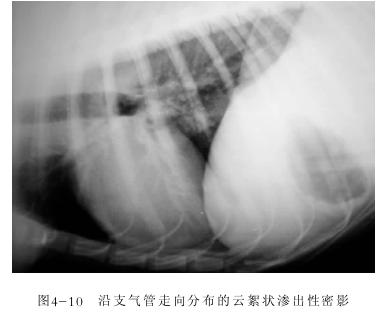

8.肺炎

肺炎的症状很明显就是咳嗽和鼻脓

除此之外,还有狗狗鼻腔会出现大量黄色分泌物。要及时做血液及X光检查。